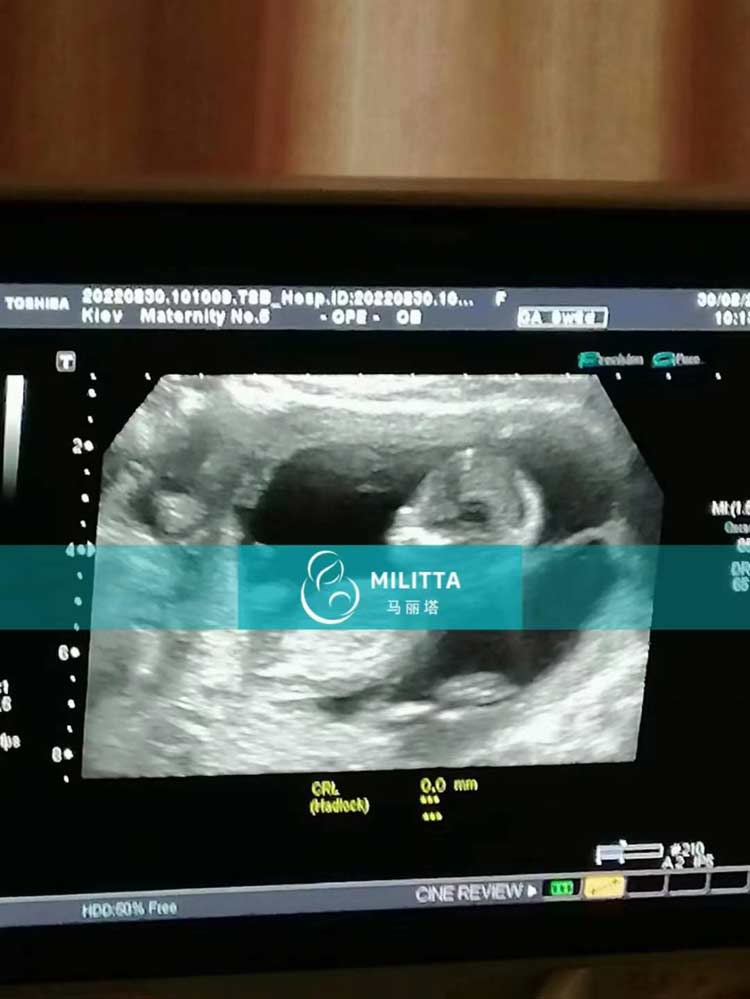

3位乌克兰试管志愿者顺利通过一次产检,胎宝宝发育的很好,B超里的宝宝们,小小的一个好可爱